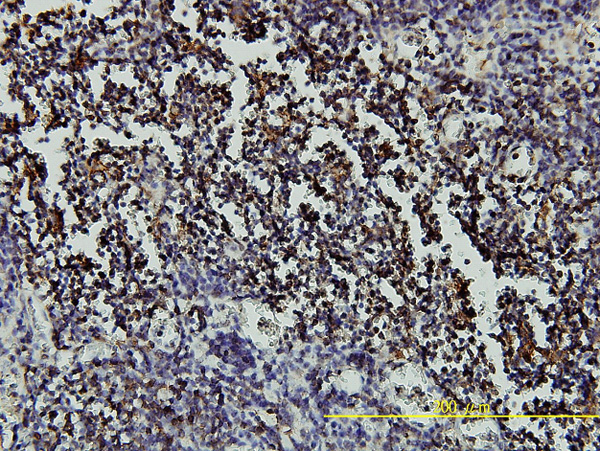

Immunoperoxidase of monoclonal antibody to RARA on formalin-fixed paraffin-embedded human lymph node tissue. [antibody concentration 5 ug/ml] |